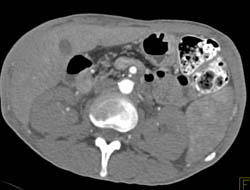

Gastric Cancer